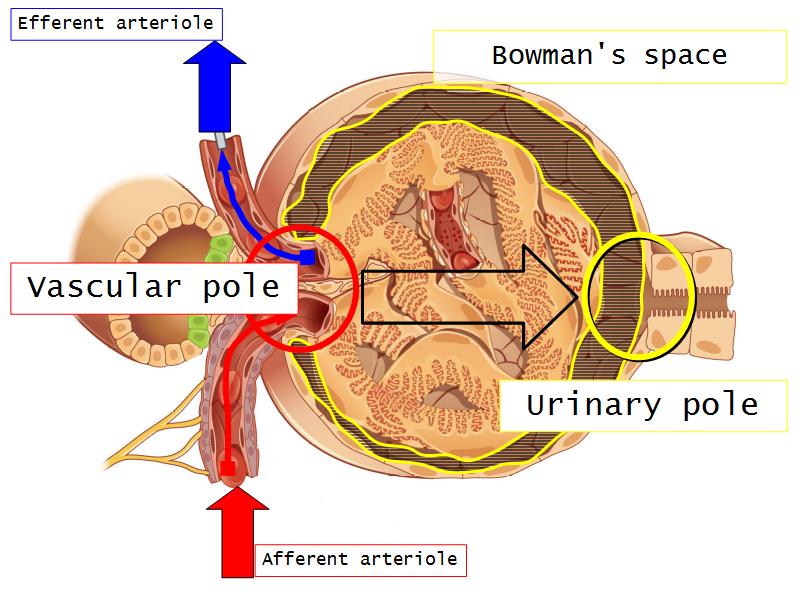

- The renal corpuscle

- Make an annotated diagram of a nephron, including the juxtaglomerular apparatus. Indicate the flow of blood and water in each part, and how solutes are filtered, secreted and reabsorbed.